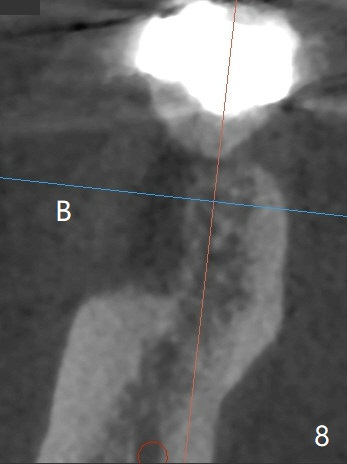

A 47-year-old man has poor dentition. The tooth #31 needs RCT, while #30 has severe PARL, especially mesial (Fig.1 M). The buccal roots are exposed (Fig.2). Between the exposed roots is the septal gingiva, which will be saved for buccal soft tissue repair (Fig.3 *). The septal gingiva will keep in place (not to be transferred) so that the recession will disappear by epithelial regrowth from the nearby gingiva (Fig.3' arrows) over the bone graft and PRF. The provisional should be fabricated to cover the soft tissue defect (Fig.3'' yellow area). In fact the mesial root fractures (Fig.4 ^), as related to the severe bony defect. There seems to be enough lingual bone to hold a 4x13 mm implant (Fig.5 green). Sticky bone (Fig.6 red circles) and PRF (blue) are to be used to repair the hard and soft tissue defects following an immediate provisional (Fig.5,6 yellow outline). Extra layer of acrylic (Fig.6 orange) will be used to cover the PRF buccally. The base of the buccal plate is thick (Fig.6 *); mesial portion appears to be denser (Fig.7 black *) than the distal one (white *). Decortication will be done if hemorrhage is insufficient. Fig.8 is a coronal section of the socket (B: buccal). Extraction (Fig.9 black area) will most likely result in a knife edge ridge. Extraction with bone graft may not fare better, as it is easy to lose the graft considering missing buccal hard and soft tissues.